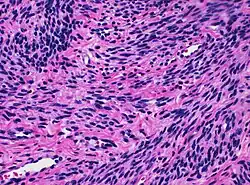

Histology of myometrium | |